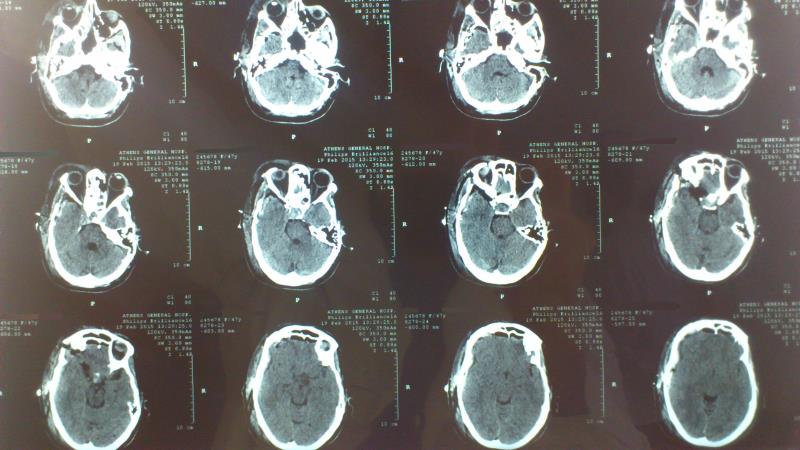

Μετεγχειρητικός απεικονιστικός έλεγχος